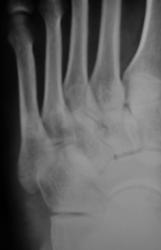

Травма.  Пациент направлен на рентгенографию стопы.

Перелом основания 5 плюсневой без смещения?

Похоже.